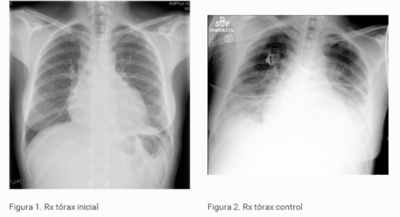

Mujer de 46 años sin antecedentes patológicos relevantes. No tiene alergia a medicamentos. Fumadora de 10 cigarros por día. Desde una semana antes de su ingreso comienza con fiebre de hasta 38º C y dolor torácico retroesternal de carácter punzante, que aumenta con la tos pero no con los movimientos y que cede con ibuprofeno. No expectoración. Pruebas complementarias: ECG: ritmo sinusal a 100 lats/min Hemograma: Leucocitos 15.39 10E3/µL, (N 89.3 %, L 4.4 %, M 4.5 %, Eo 0.7 %, B 0.2 %), Hb 11.4 g/dL, Hcto. 33.1 %, VCM 77.8 fL, Plaquetas 428 10E3/µL. Coagulación y bioquímica sin alteraciones relevantes. CPK y troponina Ic normales. La radiografía de tórax de la paciente se muestra en la figura 1. En ella lo más llamativo es la presencia de una discreta cardiomegalia. Se presenta radiografía. ¿Cuál es su diagnóstico?

Answer

• Derrame pericárdico, es la presencia de líquido en la cavidad pericárdica o derrame pericárdico apreciandose una imagen del corazón en forma de "botella“ en la Rx.

• Tamponamiento Cardíaco como como consecuencia de la acumulación de líquido a tensión, lo que anula el efecto de la presión negativa intratorácica sobre el llenado cardíaco y ofrece una resistencia a la expansión ventricular durante el llenado diastólico.

• Pericarditis aguda idiopática, en la segunda radiografía aplicada se aprecia además de la cardiomegalia datos sugerentes de derrame pleural bilateral.